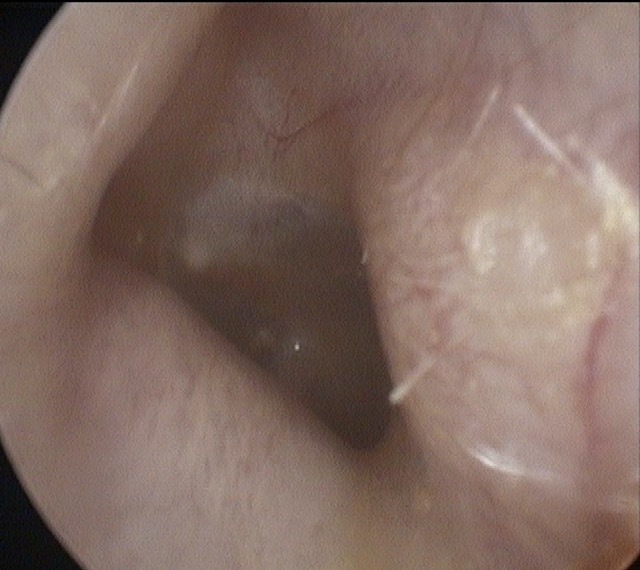

Atelectasis/Retraction

Ear Canal

Tympanic Membrane